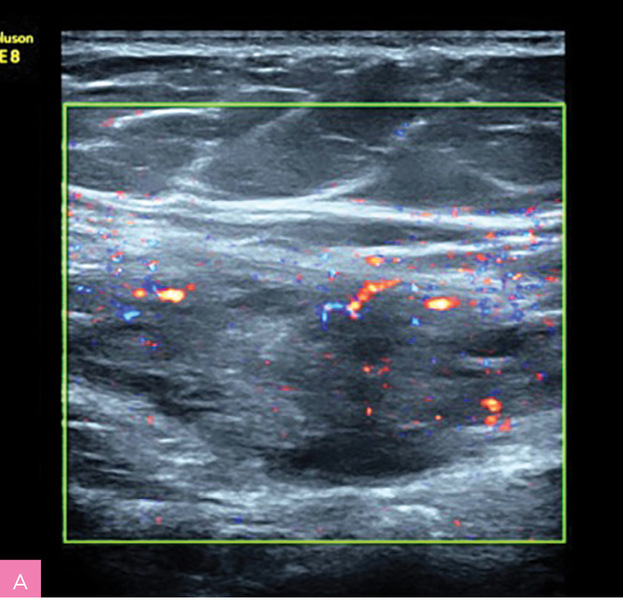

Rycina 2A, B. Obraz ultrasonograficzny zmiany endometrialnej powłok brzucha z typowym obwodowym skąpym unaczynieniem oraz odczynem wokół zmiany – obwodowe cechy włóknienia = hiperechogenna otoczka wokół guza (materiał własny autorki)

Charakterystyka wszczepów endometrialnych powłok brzucha (tab. 2; ryc. 1, 2):

- zmiany w większości hipoechogeniczne i heterogenne

- zmiany zwykle wykazują słabe unaczynienie

- średnica zmian wynosi między 5 mm a 5 cm, chociaż mogą osiągać znaczne rozmiary

- zmiany mają charakterystyczny spikularny (naciekający) obwód lub miejscowo nieregularny margines

- małe torbielowate obszary, głównie położone obwodowo – obraz drobnych torbieli krwotocznych, dające cień akustyczny

- obwodowe cechy włóknienia – hiperechogenna otoczka wokół guza.